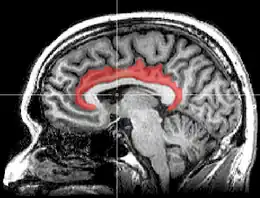

Le gyrus cingulaire est un gyrus du lobe limbique du cortex cérébral. Il est situé sur la face médiale des hémisphères, au-dessus du corps calleux. Au-dessus, il est séparé du gyrus frontal supérieur par le sillon cingulaire et du précuneus par le sillon sous-pariétal. En dessous, sa limite est le sillon du corps calleux. Au niveau du splénium du corps calleux, le gyrus cingulaire se rétrécit dans l'isthme qui se poursuit par le gyrus parahippocampique[1].

Gyrus cingulaire